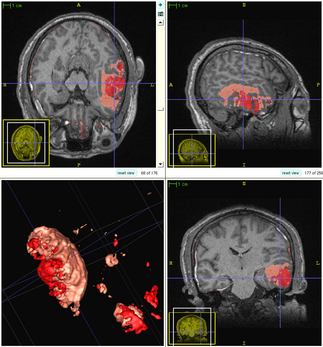

Patient-Specific Segmentation Framework for Longitudinal MR Images of Traumatic Brain Injury

We propose a multi-modal image segmentation framework for longitudinal TBI images [5]. The framework is initialized through manual input of primary lesion sites at each time point, which are then refined by a joint approach composed of Bayesian segmentation and construction of a personalized atlas. The personalized atlas construction estimates the average of the posteriors of the Bayesian segmentation at each time point and warps the average back to each time point to provide the updated priors for Bayesian segmentation. The difference between our approach and segmenting longitudinal images independently is that we use the information from all time points to improve the segmentations. Given a manual initialization, our framework automatically segments healthy structures (white matter, grey matter, cerebrospinal fluid) as well as different lesions such as hemorrhagic lesions and edema. Our framework can handle different sets of modalities at each time point, which provides flexibility in analyzing clinical scans.

Segmentation framework

The segmentation framework is initialized through manual input of primary lesion sites at each time point, which are then refined by a joint approach composed of Bayesian segmentation and construction of a personalized atlas. The following figure is the segmentation framework for multi-modal MR images.

The following two figures show the snapshot of the segmentation result.

Segmentation of acute images of subject I

Segmentation of chronic images of subject I